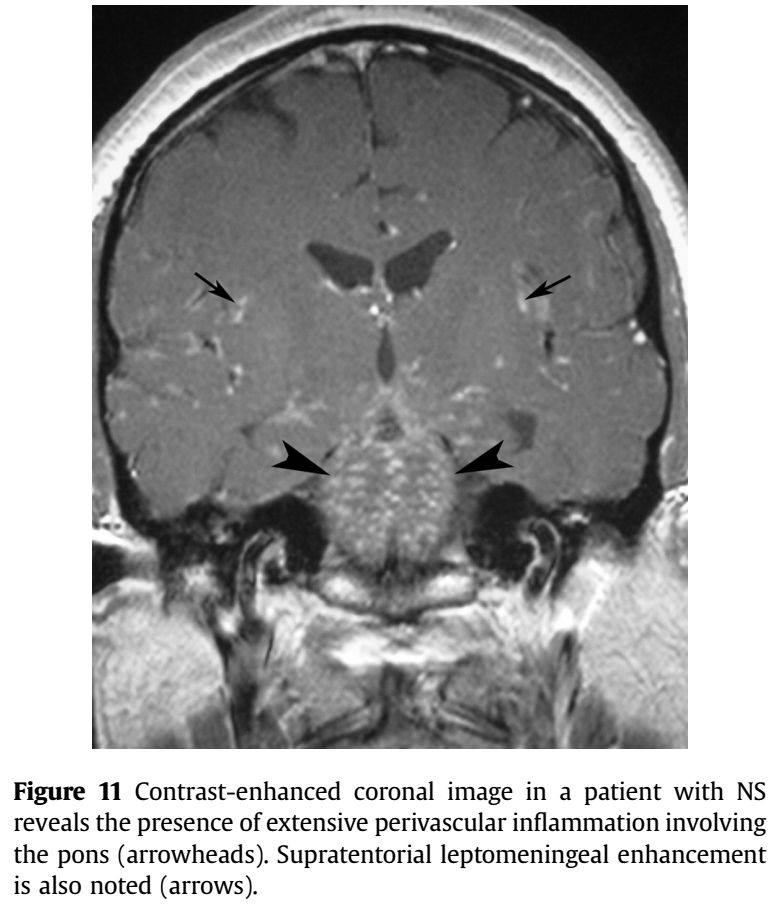

增强序列可见双侧额叶软脑膜明显强化并沿软脑膜侵入沟回,左侧颞顶交界区小片状强化;冠状位及FLAIR可见皮层皮下之白质亦有波及。该病例只有磁共振,且只有FLAIR和增强两个序列,但给人的信息量并不少:脑膜尤其是软脑膜受累突出,伴有皮层、实质损害,强化明显。感染、肿瘤、非感染性炎症都有可能,到底是什么呢?

诊断: 神经结节病

结节病是一种病因不明的多系统肉芽肿性炎症性疾病,年轻人多见。全世界的发病率各不相同,约为10-20/100,000人。它主要影响肺,皮肤和眼睛,神经系统受累约占5-20%。可以说神经结节病是罕见病中的少见表现,但其影像学具有一定的特点,也容易与其他疾病混淆,了解了这些特点在日后不期而遇时不会让它从眼皮下溜走。神经结节病影像学最突出的特点是软脑膜受累,但只知道软脑膜是不足以全面掌握神经结节的影像学表现,关于神经系统其他受累部位及鉴别诊断如下图:

➤脊髓受累:

五花八门的受累部位和表现让人看花了双眼,万变不离其宗,颅底为主的软脑膜受累以及沿血管间隙的强化,以及各种肉芽肿样强化,都应该考虑到神经结节病的可能,但因其少见,不要忘了最基础的诊断原则,首先应当谨慎与其他更常见的疾病相鉴别。